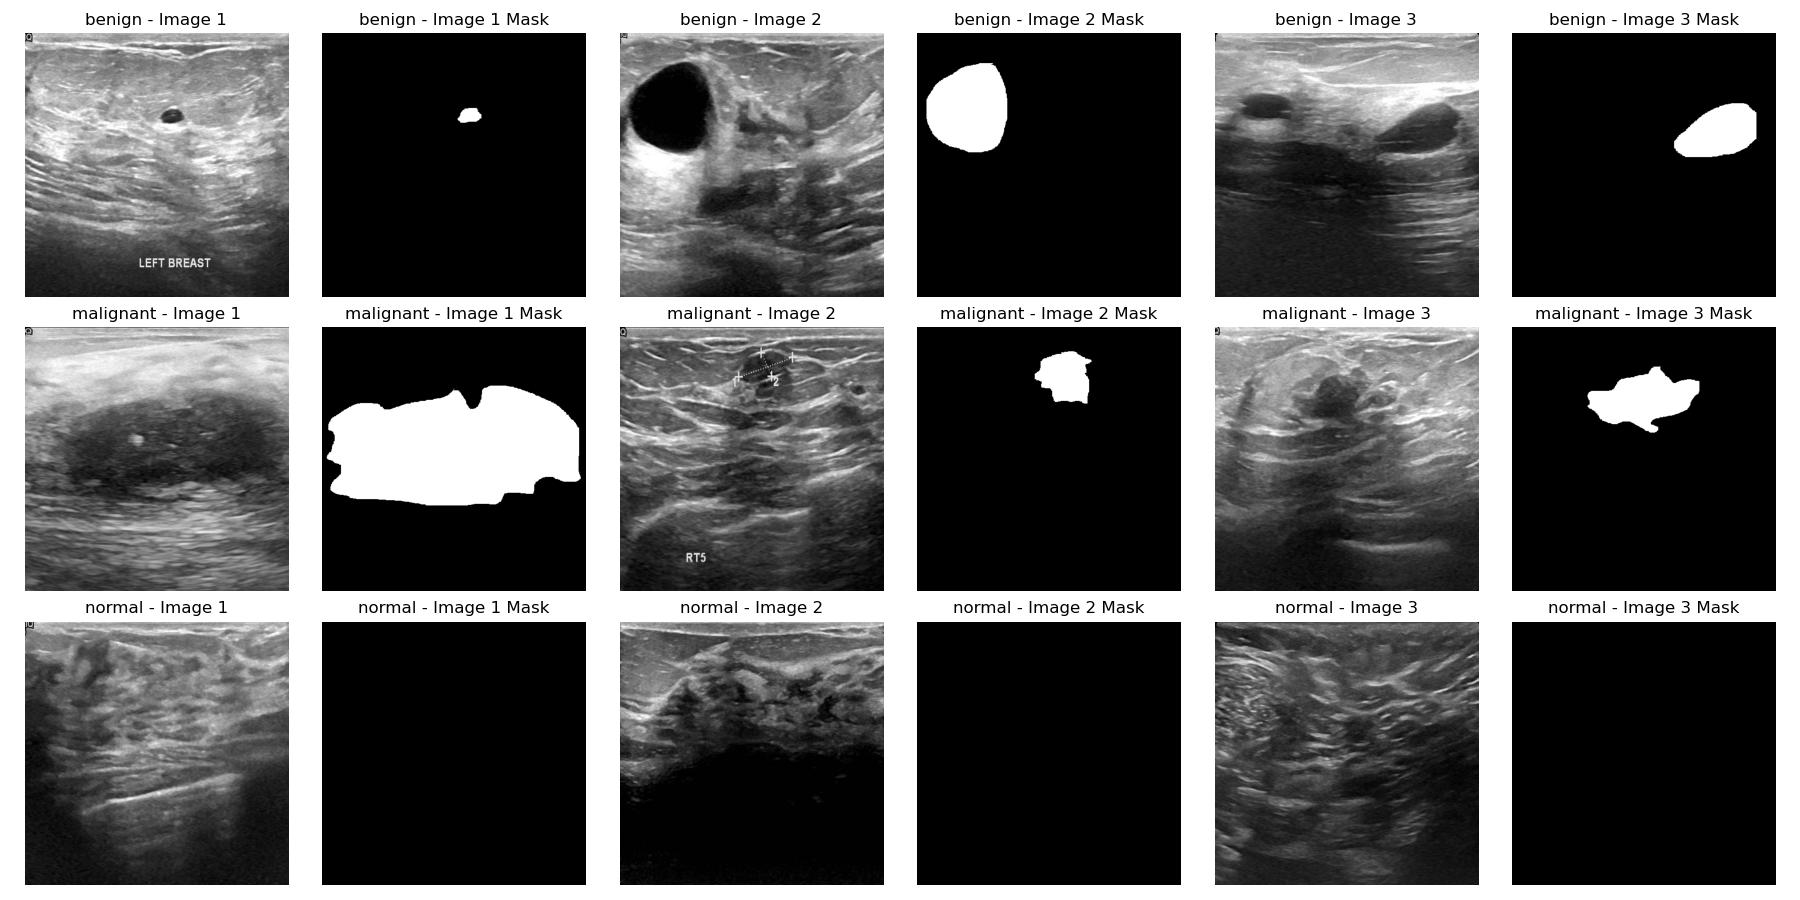

시각적으로도 normal 클래스에서는 종양이 관찰되지 않고, malignant 클래스와 benign 클래스에서는 관찰됨이 확인된다.

malignant클래스와 benign클래스간에는 선명도 정도의 차이가 있는 것이 대략적으로 확인되었다.